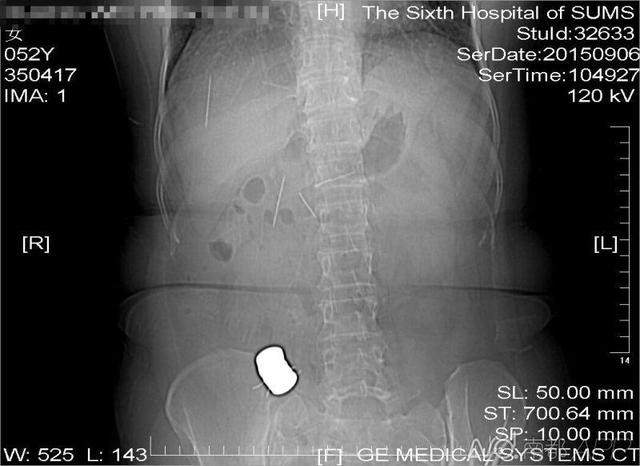

沒想到經醫院拍下X光片後,發現老婦肚裡全是針和磁鐵,醫院擔心引發多發性腸穿孔,便趕緊替她開刀;主治醫師表示,黃婦肚裡的針和磁鐵散布在腹腔內,「其中一塊上面還吸了好幾根針,但有一根插進胰腺,每根針大概有4公分長」。

整個手術共費時了8小時,醫療團隊終於在「腸海」中撈起了9根針與9塊磁鐵,剩下的那一根因為卡在胰腺組織內,和組織黏在一起,取出來反而會傷到胰腺,引起更嚴重的併發症,便決定讓它留在肚內,定期觀察。